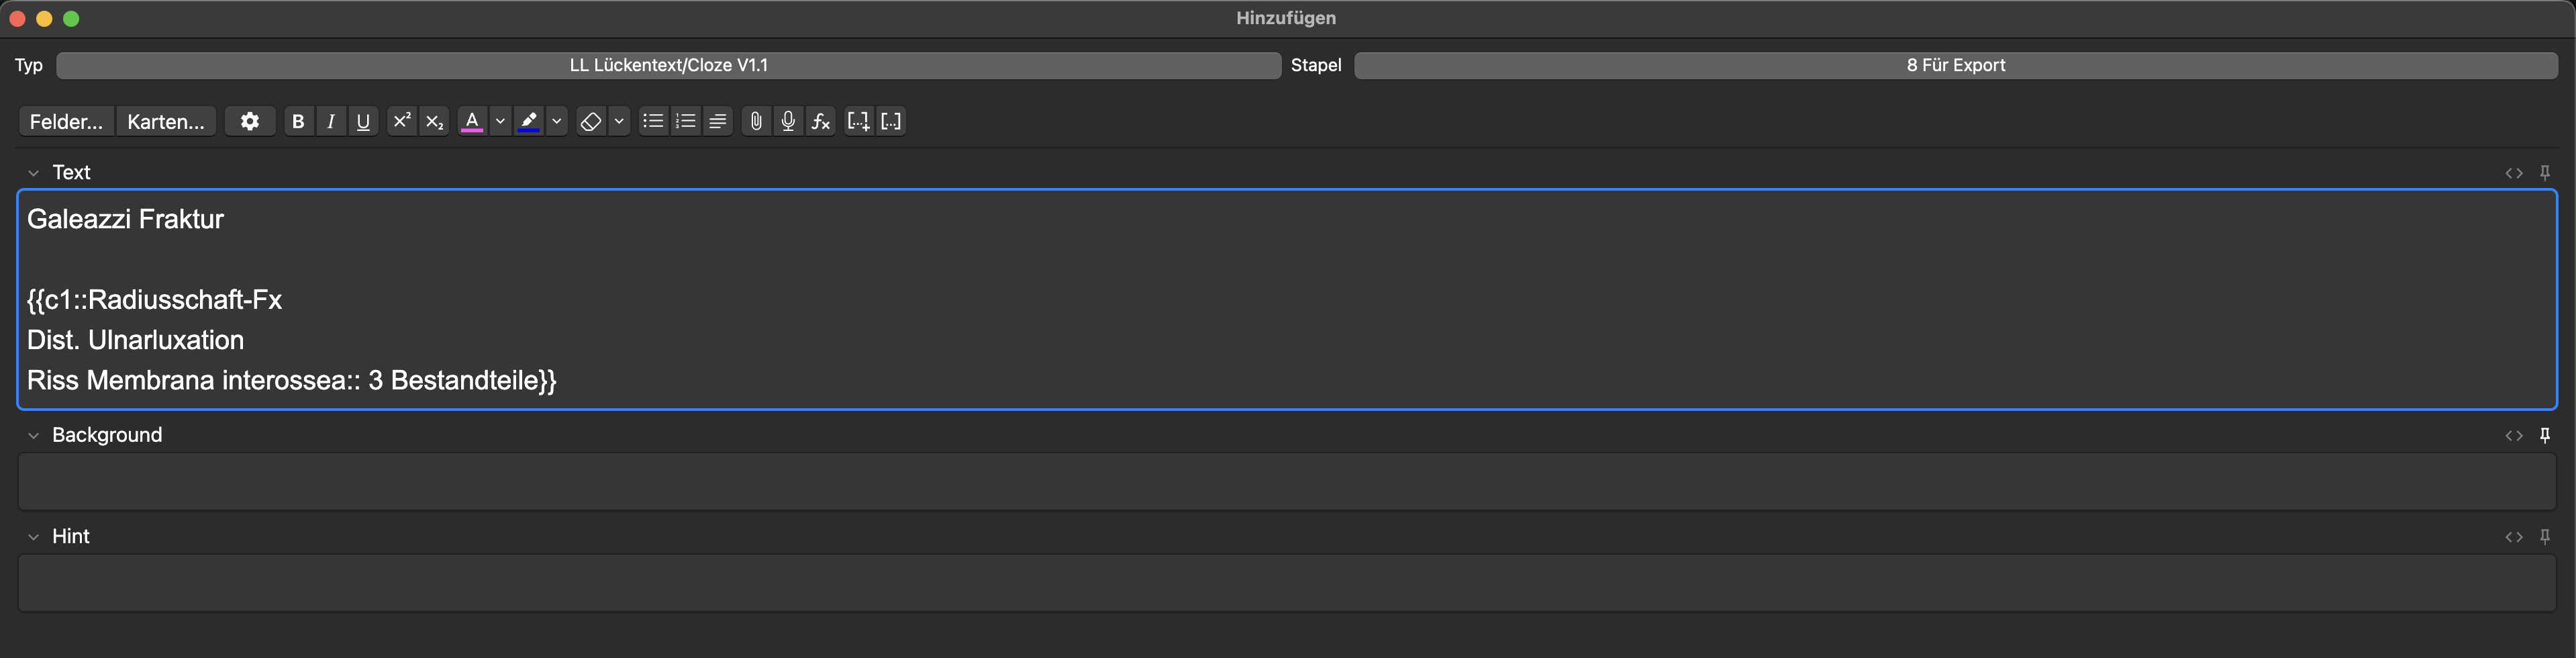

- Defi.: Bestandteile eines medizinischen Terminus – z. B. Galeazzi-Fraktur

Wenn dadurch mehrere Items abgefragt werden, sollte die Anzahl kenntlich gemacht werden, um deinem Gehirn eine komfortable mentale Antwort-Fahrbahn zu ermöglichen:

Die abzurufende Information „3 Bestandteile“ kann auch in Blau in der Klammer vor Beantwortung der Frage dargestellt werden. Dazu ::3 Bestandteile hinter die Antwort einfügen (der :: erlaubt diese Funktion). Das ist eine Präferenzfrage; ich mache es gerne so:

Weiteres Beispiel: